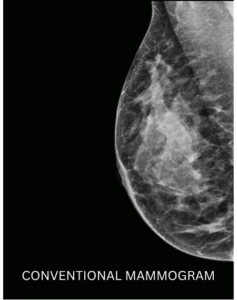

A Contrast Enhanced Mammogram (CEM) is similar to having a conventional mammogram but with the addition of a contrast enhancing IV dye containing iodine (the same dye as used in CT scans) to make it easier to characterise breast abnormalities and detect cancers that may not be visible in a standard mammogram. A doctor may refer you for a Contrast Enhanced Mammogram if you are at an increased risk of developing breast cancer, have dense breast tissue, or as an alternative to MRI.

Contrast Enhanced Mammography allows clinicians to see certain lesions and abnormalities that conventional mammography cannot detect – especially in patients at increased risk of breast cancer or who have dense breasts or implants.